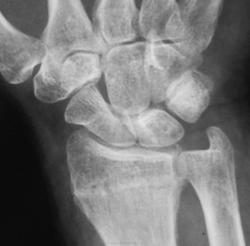

Боли. Травма в анамнезе была, но за помощью не обращался.

Похоже вколоченный перелом диафиза лучевой кости.

Перелом метаэпифиза луча

консолидированный вколоченный перелом метаэпифиза лучевой кости